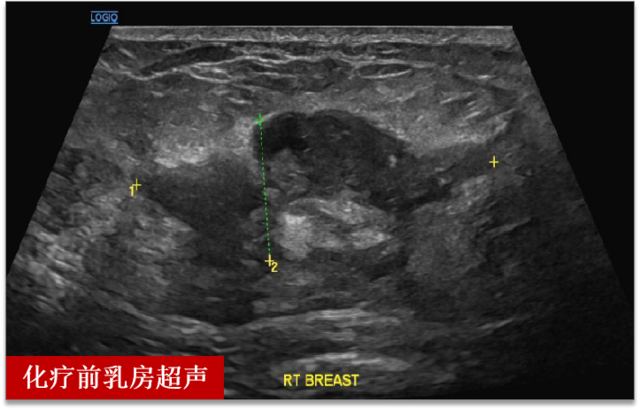

王女士(化名),半年前发现右乳肿物

没有引起重视,近来发现肿块明显增大

检查后发现肝部多发占位

经过穿刺后病理确诊乳腺癌伴肝脏转移